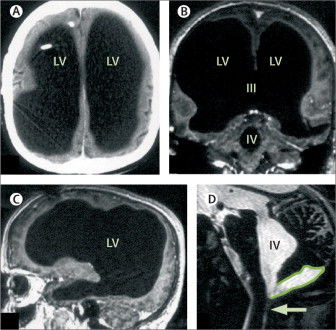

Bệnh nhân người Pháp phải nhập viện sau khi cảm thấy chân trái của mình yếu đi trong hai tuần. Trong quá trình chẩn đoán bệnh, ông được thực hiện nhiều xét nghiệm. Các bác sĩ đã vô cùng ngạc nhiên khi ảnh chụp não của não của bệnh nhân lại không phải não mà là một khoang chứa đầy chất lỏng khổng lồ.

Ảnh chụp não toàn chất lỏng của bệnh nhân

Thế nhưng kết quả quét não đã khiến tất cả phải giật mình. Não bộ của ông đã sưng lên quá nhiều, chứa đầy dịch tủy, và thứ dịch ấy gần như đã thay thế toàn bộ khối óc, chỉ để lại một lớp vỏ não mỏng chứa các neuron thần kinh. Nói cách khác, người đàn ông này gần như không có não.

Việc chất lỏng lưu thông khắp não là bình thường. Tuy nhiên ở trường hợp này, thay vì được đưa vào hệ thống tuần hoàn, chất lỏng trong não người đàn ông này tích tụ lại. Cuối cùng, sự tích tụ chất lỏng chiếm hết không gian trong sọ, chỉ có một lượng siêu nhỏ là não thực sự.